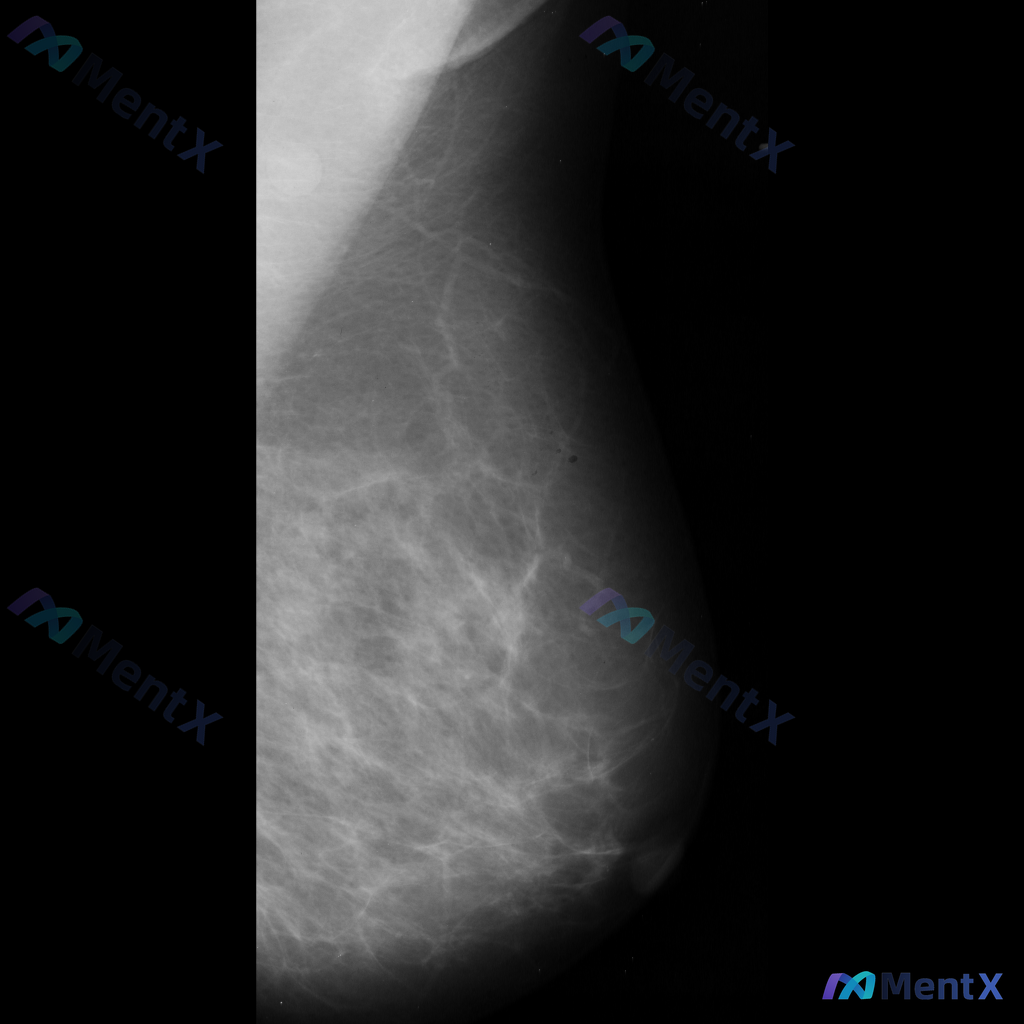

整理到一份单侧乳腺钼靶MLO位的影像资料,想和大家讨论一下初步判断思路。 影像基本情况 - 投照位置:单侧乳腺MLO位 - 主要表现:乳腺组织不均匀致密,ACR BI-RADS c类;在致密的腺体背景下,可见部分区域的致密影,但边界比较模糊,暂不能明确界定为独立肿块。 目前只有这一个位置的影像资料,...

整理到一份乳腺钼靶影像的分析素材,目前是单侧MLO位的读片结果: 影像所见描述: - 观察到的结构均在正常乳腺组织范围内 - 未发现恶性或高度可疑恶性特征的肿块、钙化、结构扭曲、不对称等表现 - 腺体组织较为丰富 单看目前这份单侧MLO位的分析,大家会怎么判断?后续如果要给出完整的评估建议,你会优先...